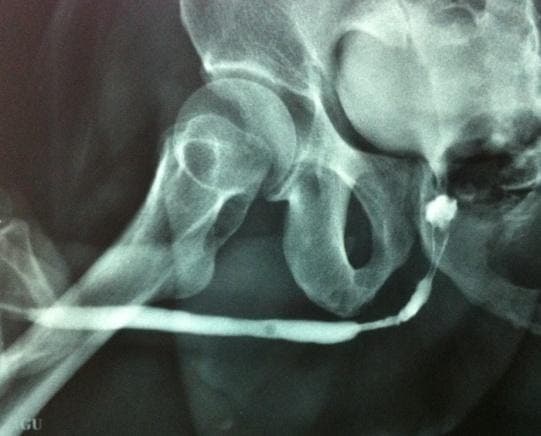

Ascending urethrogram USG Cysto-urethroscopy Clean Intermittent Self Catheterization (CISC) Redo TURP Bladder Neck Incision (BNI) Urethral Dilatation Visual Internal Urethrotomy (VIU) Uttarbasti Calibration Oral medication

Many patients suffer bladder neck stenosis, urethral stricture, or incontinence after TURP.